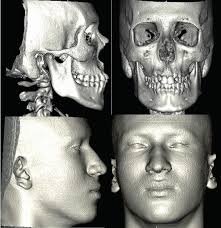

Saiba as diferenças, finalidades e custo-benefício entre os principais exames de imagem utilizados na medicina.

Entenda de forma simples a física por trás do raio-X, tomografia e ressonância magnética.